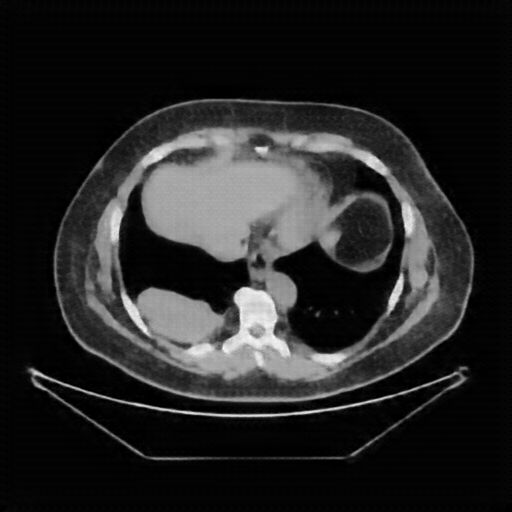

Image Grid

4Γ—3 grid: Rows show different image types (Original NATIVE, Reconstructed NATIVE, Original VENOUS, Generated VENOUS), Columns show windowing techniques (No Window, Lung Window, Mediastinum Window)

Original NATIVE CT scan (input)

Full window (WL 1023.5, WW 4095 β†’ Low βˆ’1024, High +3071)